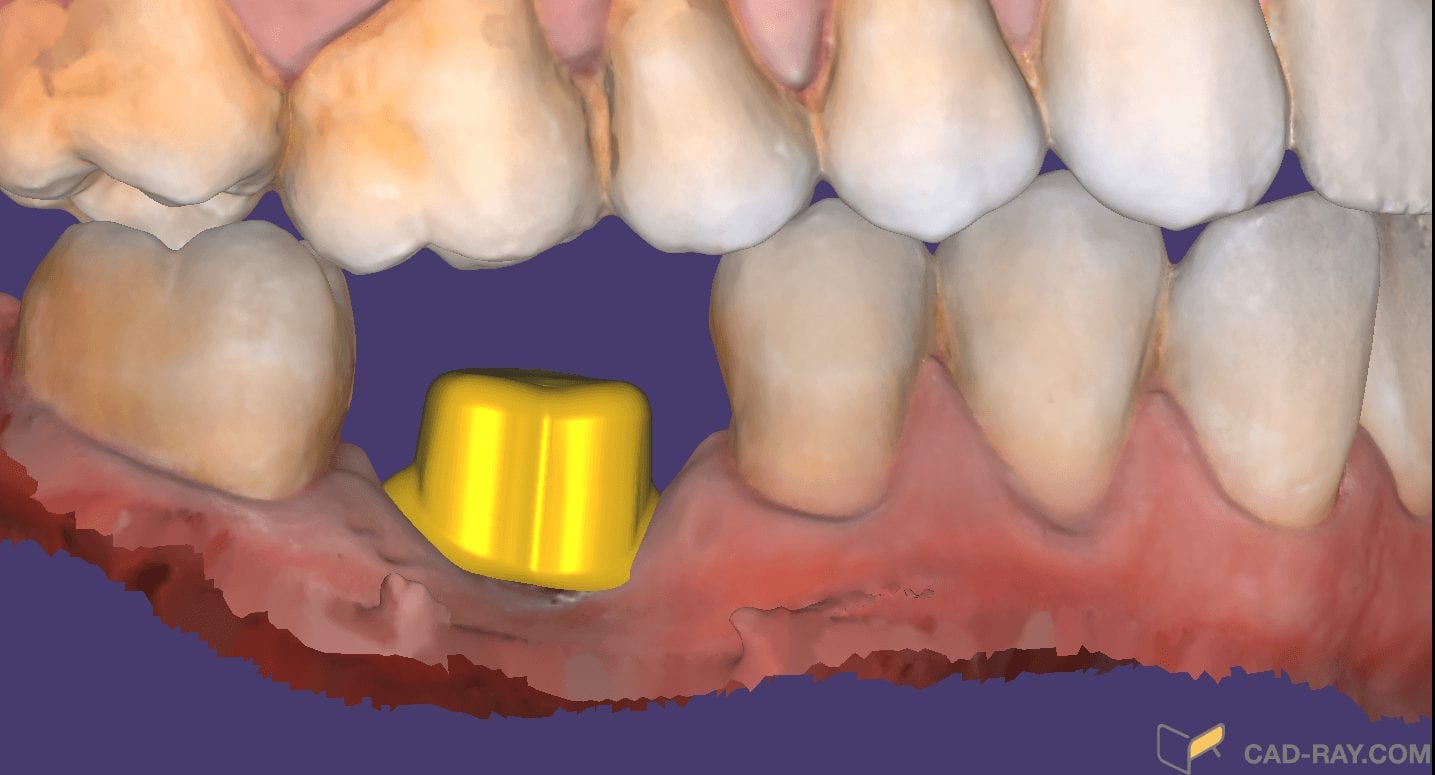

Support Pins for your Models for Oral Appliance Fabrication

May 29, 2019A friendly reminder- this case was table top scanned with a desktop scanner so don’t get distracted, but be aware that for oral appliances, particularly for apnea treatment or bruxism, […]